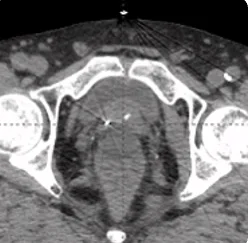

215 cc prostate post-CT showing BioProtect Balloon Spacer, prostate, and rectum.

Post-CT

Image courtesy of Dr. Shawn Zimberg, Radiation Oncologist.